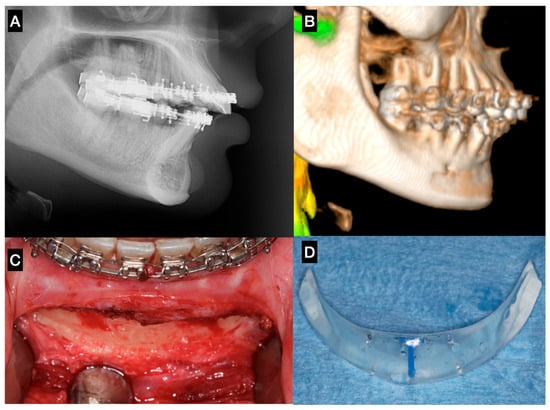

Reconstructing the Head and Neck region presents some of the most complex challenges in surgery, requiring not just technical precision but also creativity, collaboration, and innovation. In recent years, we’ve seen incredible progress thanks to advancements in areas like 3D printing, virtual surgical planning, augmented/mixed reality, artificial intelligence, tissue engineering, and biomaterials. Yet, while the tools at our disposal are more advanced than ever, the challenge remains: how do we translate innovation into better outcomes for our patients?

This Special Issue aims to bring together fresh insights, groundbreaking research, and real-world clinical experiences that are shaping the future of oral and cranio-maxillofacial reconstruction. We welcome contributions that explore novel surgical approaches, digital tools, regenerative techniques, and interdisciplinary strategies that improve both function and aesthetics for patients. Whether you're working at the bench or the bedside, we hope this collection will serve as a platform for sharing ideas that push the boundaries of what's possible in this evolving field.